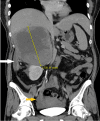

Figure 4

Figure 4. CT scan abdomen (coronal view) obtained at the emergency department

The image is showing retro-peritoneal (white arrow) and intraperitoneal (yellow arrow) hemorrhage from the tumor.